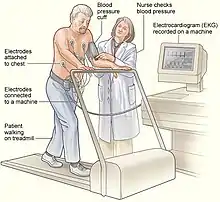

Exercise and other provocative testing

Exercise testing, commonly performed on a treadmill or stationary bicycle, can help to diagnose CPVT. During the test, those with CPVT often experience ectopic beats, which may progress to bidirectional and then polymorphic ventricular tachycardia as the intensity of exercise increases.[23] Some of those suspected of having CPVT, such as young children, may not be able to perform an exercise tolerance test. In these cases, alternative forms of testing include adrenaline provocation testing, during which adrenaline is infused into a vein at gradually increasing doses under close supervision and ECG monitoring.[22] Additionally, long term or Holter ECG monitoring can be performed, although this form of testing is less likely to detect an arrhythmia. Invasive electrophysiological studies do not provide useful information to help diagnose CPVT or to assess the risk of life-threatening arrhythmias.[2][22]